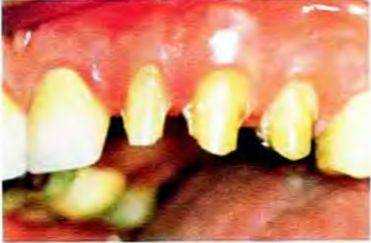

Рис. 13-44. Клык и боковой резец верхней челюсти препарированы под металлокерамические коронки

Рис. 13-45. Окклюзионный вид гипсовых моделей тех же зубов. На вестибулярной поверхности хорошо визуализируются гладкие уступы равномерной ширины. Скос уступа не препарировали. поскольку планируется изготовить металлокерамические реставрации с цельнокерамическим вестибулярным краем